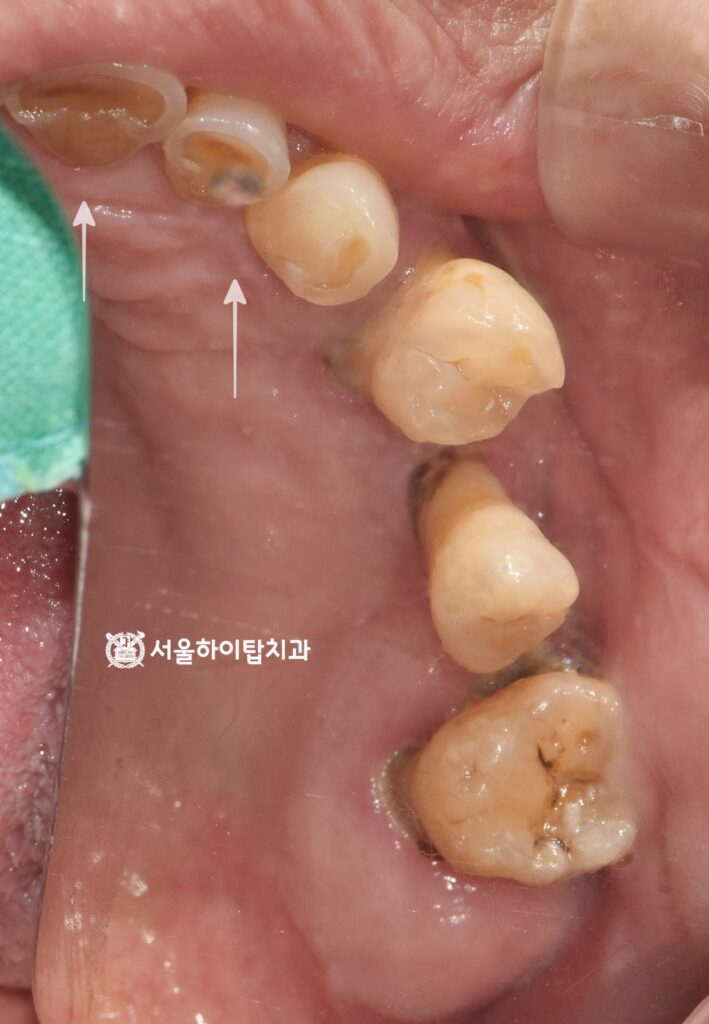

입을 다물었을 때 보는

측면, 정면 사진에서도

정출되어 치근이 보이는 모습과

출혈, 잇몸 부종, 전치부 마모 등

전형적인 심한 치주염의 양상을

보여주고 있습니다.

빠른 치료가 요구되는 상황입니다.